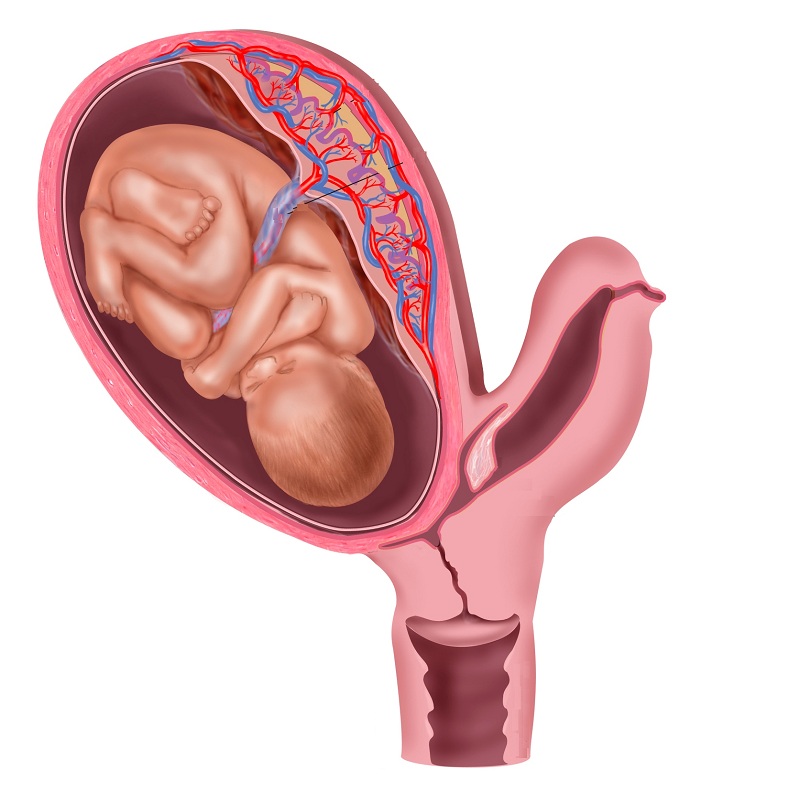

Анатомия женского организма: строение и функции матки

Раздел: Фотопуть к знанию